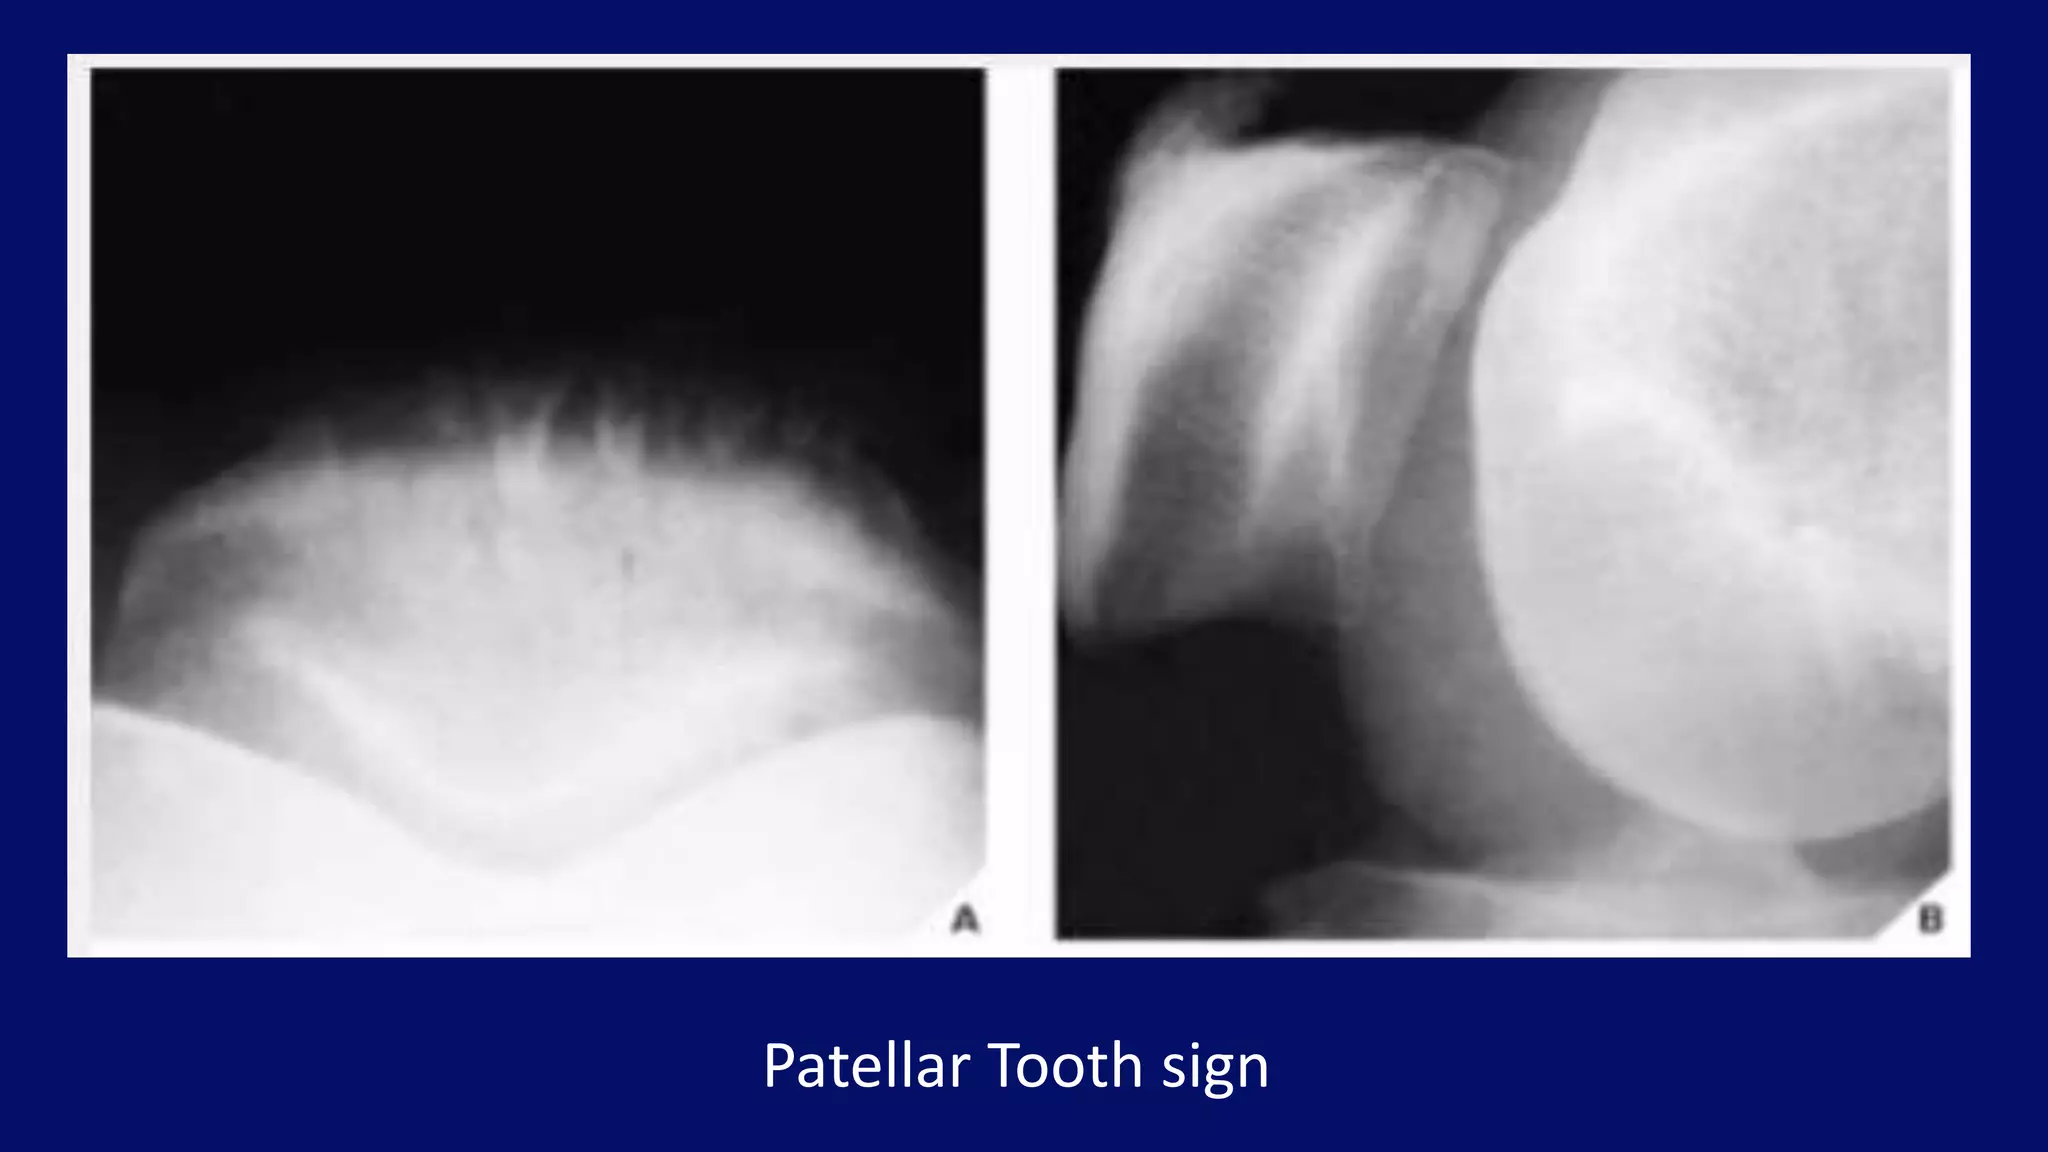

Patellar Tooth sign

Patellar Tooth sign on AP projection

• #27 Lateral radiograph of the knee (A) and axial radiograph of the patella (B) of a 72-year-old woman demonstrate narrowing of the medial femoropatellar joint compartment and osteophyte formation on the medial aspect of the joint.

• #28 (A) Axial view of the patella demonstrates dentate structures (the “tooth” sign), which represent degenerative ossifications (enthesopathy) at the insertion of the quadriceps tendon into the base of patella, as seen on the lateral view(B) in this 55-year-old man.

• #29 Occasionally, the tooth sign can also be demonstrated on the anteroposterior projection of the knee, seen here in a 54-year-old woman.